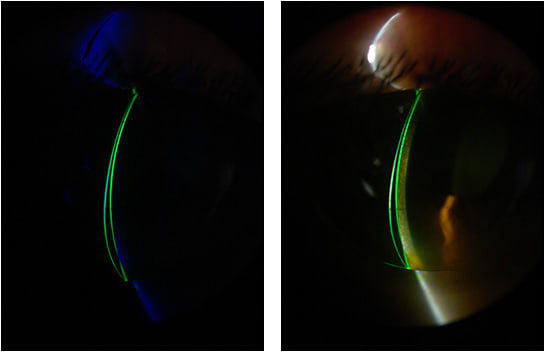

We schedule three follow-up evaluations for first-time GP lens patients within 10, 30, and 90 days from the dispensing day. This is time enough to make adjustments to the fit and also to prevent interruption of the adaptation process. Figure 4 shows the final lens dispensed to the patient in higher magnification with a cobalt blue filter and fluorescein. A video of the fit is available below.